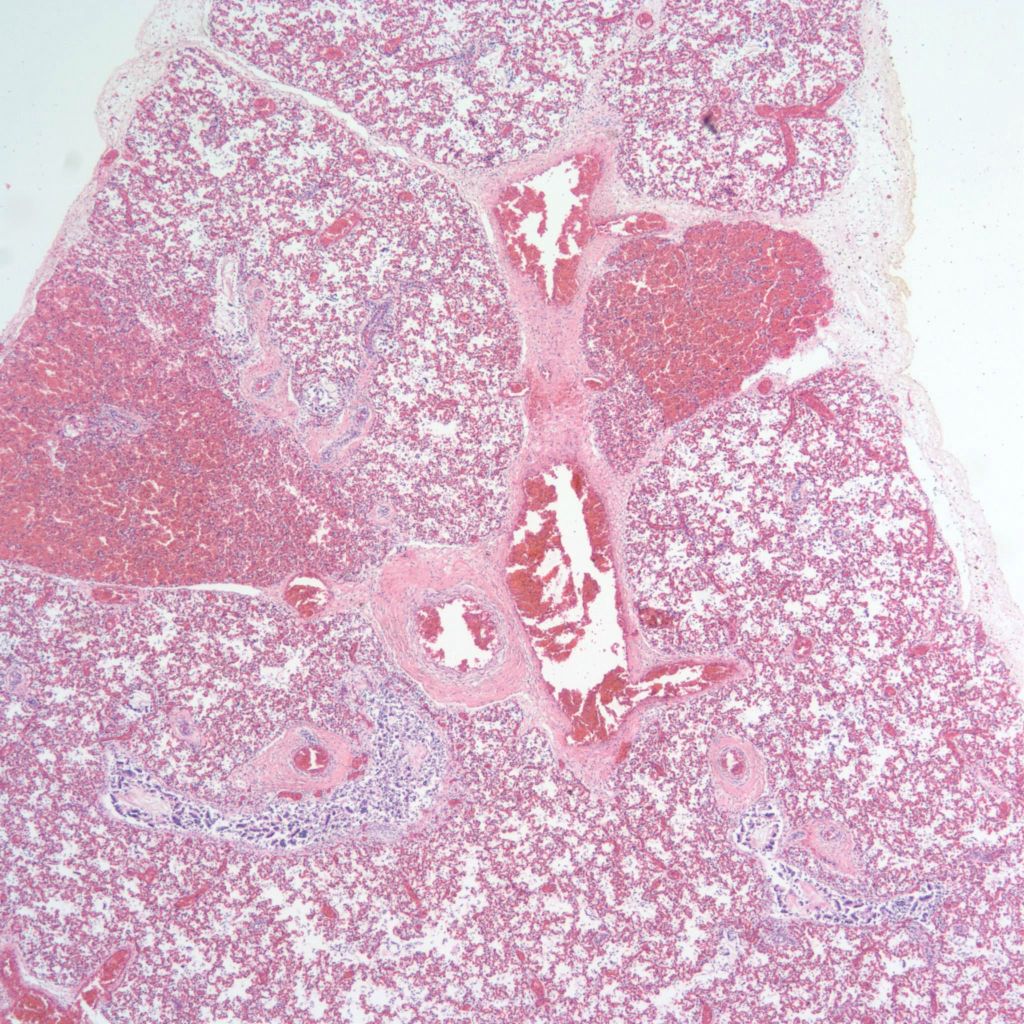

Pulmonary hypoplasia: Pulmonary hypoplasia may be apparent on opening the chest because the small lungs are obscured by the heart (Fig 1a,b).

The lung lobules should be identified noting three on the right and two lobes with a lingua on the left (Fig 2).

After opening the bronchi and pulmonary arteries, the lungs can be cut off at the hilum and weighed separately. The combined lung weights can be evaluated by the lung to brain weight ratio, but pulmonary hypoplasia is defined by the lung to body weight ratio. Above 28 weeks of gestation the lung: body weight ratio below 0.012 ratio is evidence of pulmonary hypoplasia1. Below the gestation the cut off is 0.015.